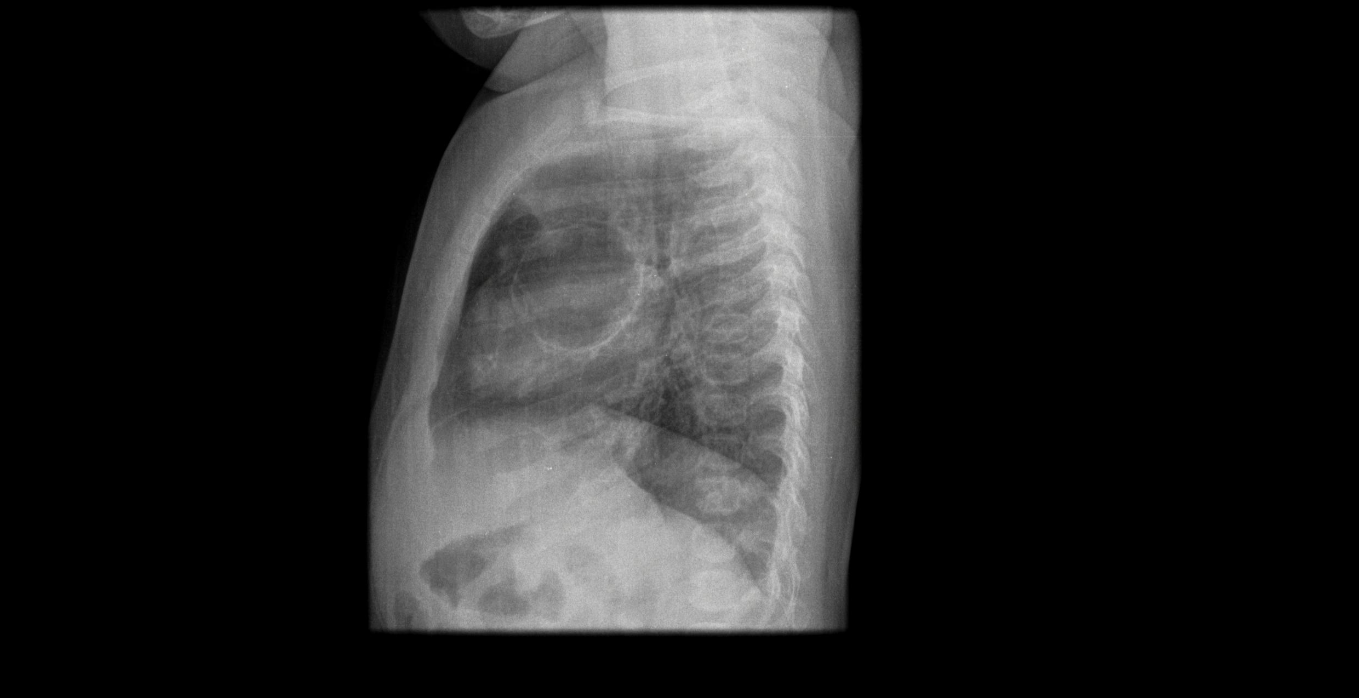

Paciente de 12 años con dolor abdominal. Remitida para estudio de masa intraabdominal.